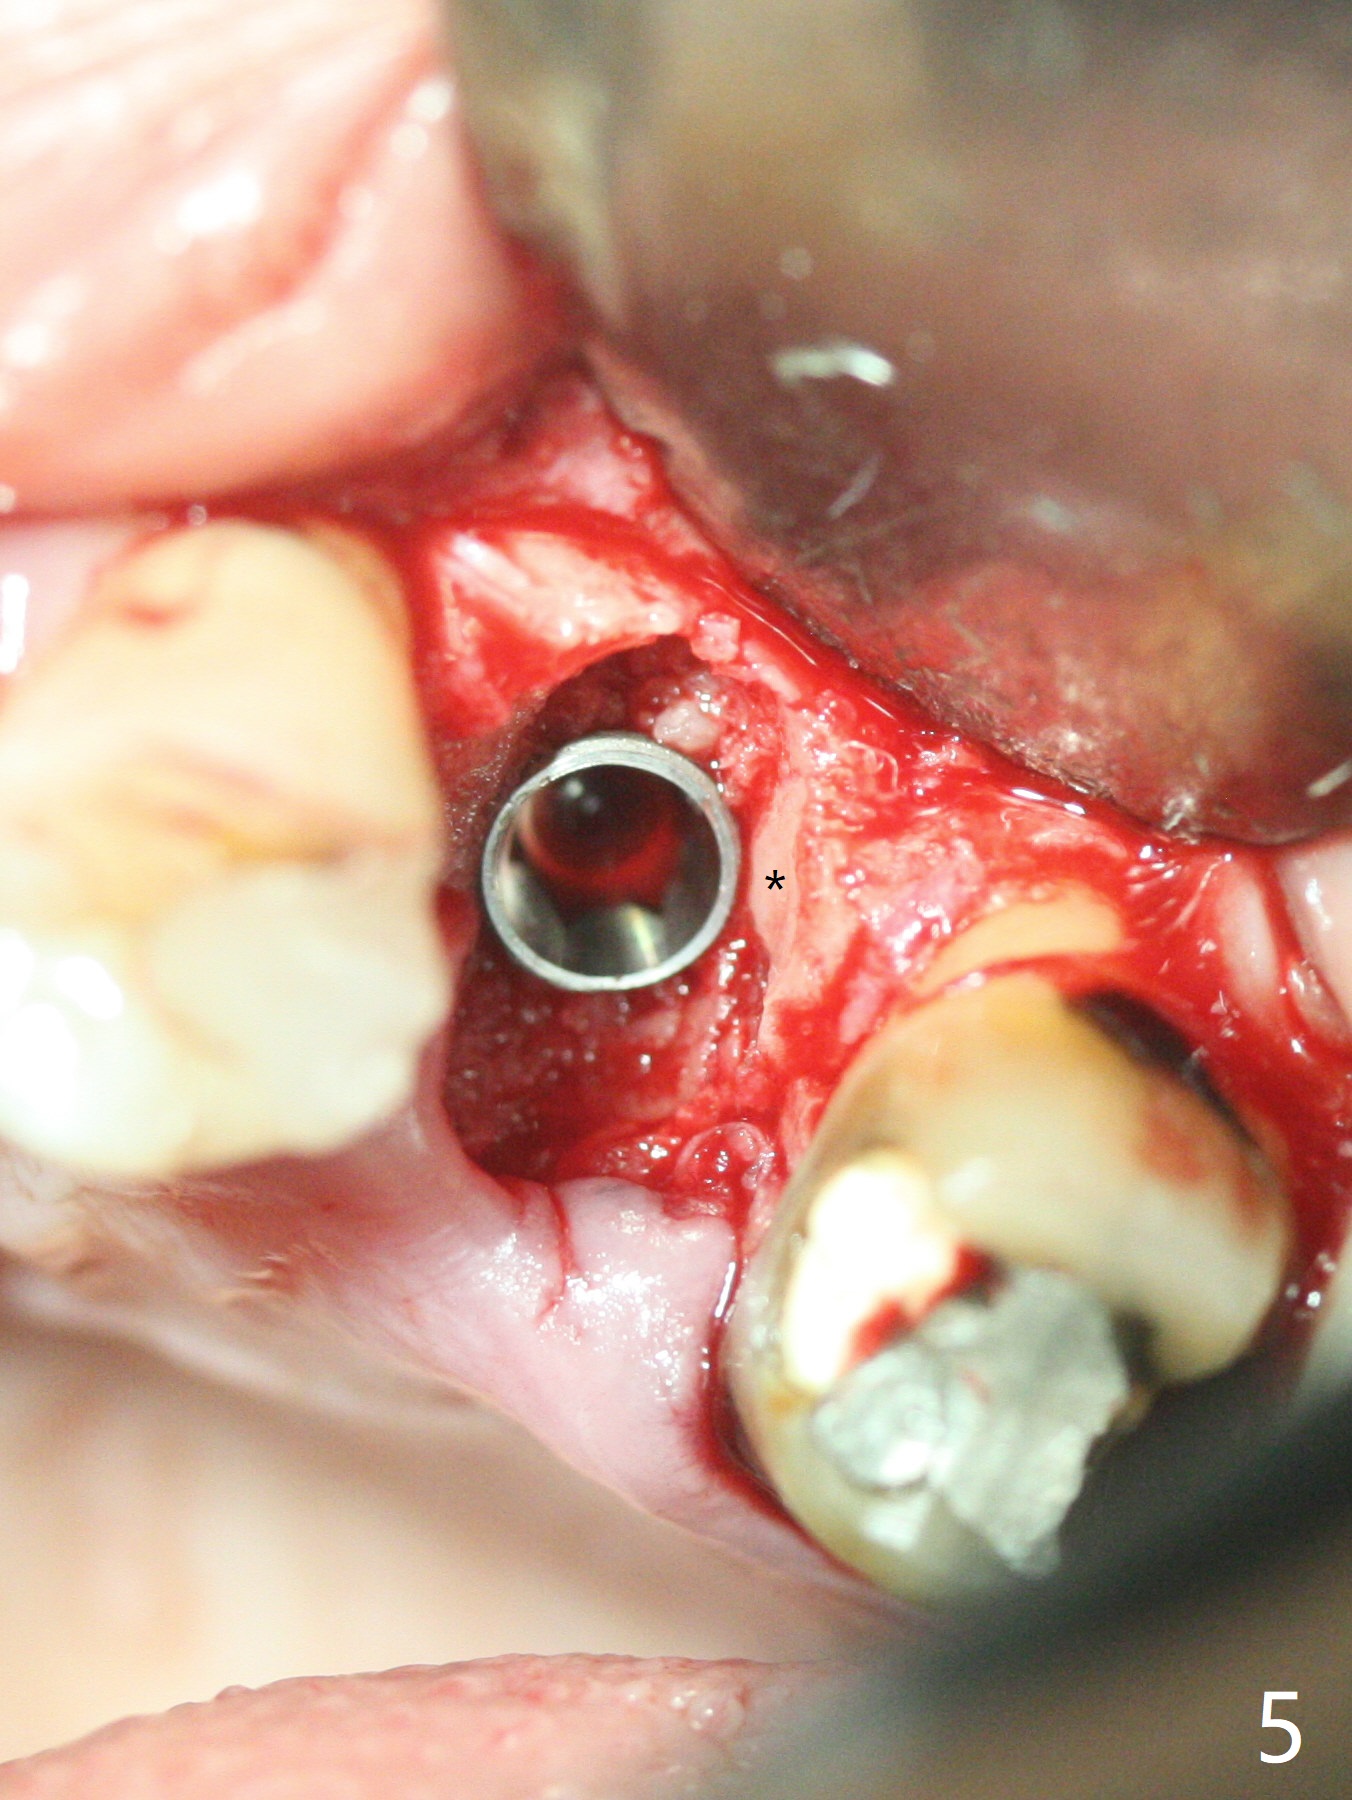

The patient with the anterior cross bite at the left lateral and canine and incipient Class V caries returns to clinic for #13 residual root extraction (Fig.1,2). There is no quality root structure (Fig.2) or space (Fig.3) for socket sheath. Two amalgam carriers of Vanilla is inserted and pushed by the 4x11 mm dummy implant for sinus lift (Fig.4 *). When the same sized final implant (4x11 mm) is placed, a 5.5 mm bone profile drill is used to trim the proximal crests (Fig.5 * sticky bone packed in the buccal and palatal gaps). In fact the implant turns when a 4.5x4(3) mm pair abutment is tightened. The implant is backed up; with a healing screw, sticky bone is placed (Fig.6 *) and then covered with a piece of PRF and a part of GEM cap. The wound is sutured with 4-0 PGA; periodontal dressing is applied. The implant is somewhat over-seated without the bone graft covering the apical end of the implant (Fig.7, as compared to Fig.4). A 4.5 mm implant should be placed. The GEM Cap appears to be absent 9 days postop, while the periodontal dressing dislodged in 1 week (Fig.8). It appears that the existing abutment at #15 is incompletely seated (Fig.3, 5.5x4(2) mm). After use of 5.5 and 6.0 mm bone profile drills, a 5x4(3) mm abutment is placed with 35 Ncm torque. In fact the bone graft coronal to the implant remains (Fig.9 *) in spite of apparent loss of the overlying PRF and GEM cap (Fig.8). After use of a 4.6 mm profile drill, a 5.5x3 mm healing abutment is placed 4.5 months postop (Fig.10). Without a provisional at #13 for ~ 4 months, there is a gap between crowns at #14 and 15 (not shown due to angulation). Impression is taken for #13 crown fabrication 5.5 months postop and for #15 crown repair (addition of porcelain for the mesial contact, Fig.11). It appears critical for a provisional to maintain the position of the neighboring tooth.